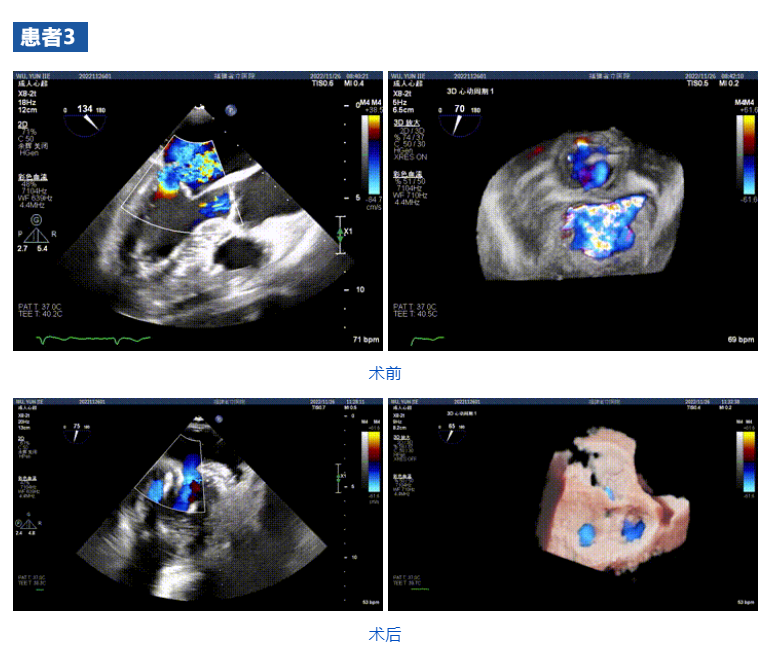

接受治療的三例患者均為器質(zhì)性重度二尖瓣反流(DMR)患者,術(shù)前超聲提示二尖瓣后葉脫垂伴4+反流,左室舒張功能減退。郭延松教授攜同團(tuán)隊(duì)成員陳新敬副教授和洪景宣、方明程、楊清勇主治醫(yī)師、心外科丁杭主任以及超聲科賴(lài)寶春、葉振盛主治醫(yī)師共同進(jìn)行病情討論??紤]到患者高齡、基礎(chǔ)疾病多、STS評(píng)分高,為外科手術(shù)極高?;颊?,不適合進(jìn)行外科開(kāi)胸二尖瓣手術(shù),因此決定為患者實(shí)施經(jīng)導(dǎo)管緣對(duì)緣修復(fù)介入術(shù)(JensClip經(jīng)導(dǎo)管瓣膜夾系統(tǒng))。

在浙江大學(xué)醫(yī)學(xué)院附屬第二醫(yī)院王建安教授團(tuán)隊(duì)的支持下,手術(shù)經(jīng)股靜脈-房間隔入路,采用全身麻醉插管,在TEE和DSA引導(dǎo)下完成房間隔穿刺。置入JensClip瓣膜夾系統(tǒng)后,在左房調(diào)整瓣膜夾的位置和軸向,后進(jìn)入左室,在TEE引導(dǎo)下捕捉二尖瓣前后瓣葉,并關(guān)閉瓣膜夾。經(jīng)TEE反復(fù)確認(rèn)手術(shù)效果后最終鎖定并釋放瓣膜夾。術(shù)后即刻超聲顯示瓣膜夾位置穩(wěn)定,功能良好,二尖瓣反流由術(shù)前4+減少至微量,手術(shù)圓滿成功。